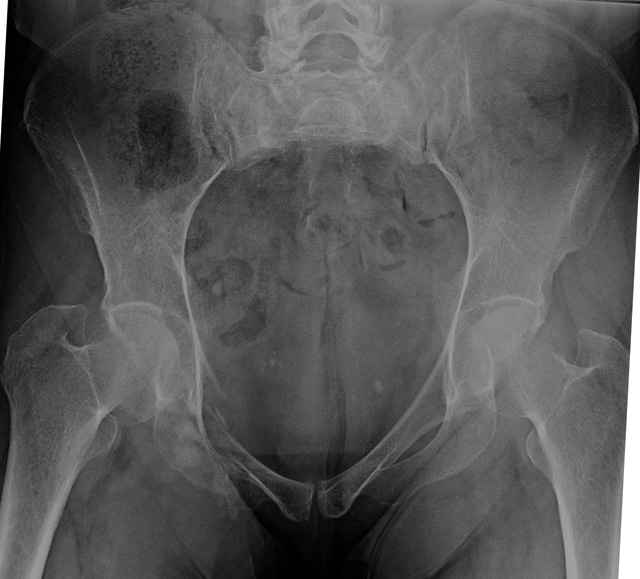

Here are a recent patient’s example slides...

54 yo Female Fell c/o Pain

Initial Films

?Instability on Exam - Limited by Pain

NonOp Initial Mgmt

3 Months After Fall

Continued Pain & Immobility

(+) Instability to Compressive Manual Exam